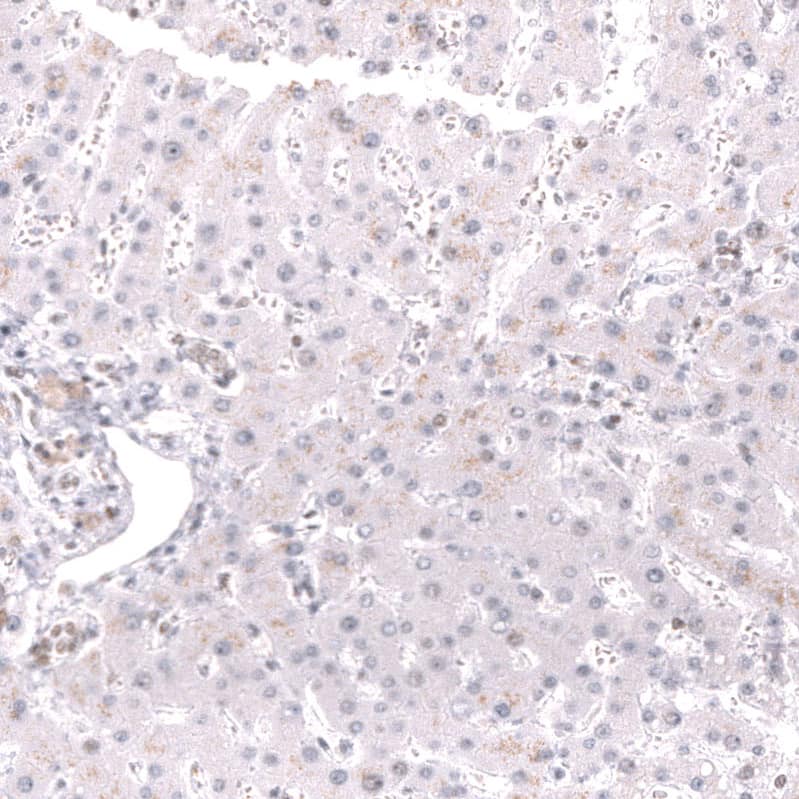

Immunohistochemistry-Paraffin: MSH2 Antibody (CL13724) [NBP3-24573]

Staining of human ovarian cancer (high grade serous carcinoma) shows strong nuclear positivity in tumor cells.